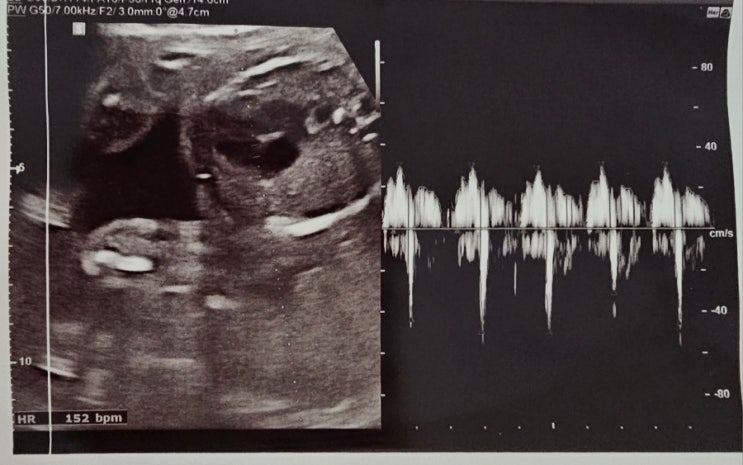

임신 23주 5일 초음파, 경부길이

2023.08.17. 세브란스 다녀온 지 벌써 2주! 지난번에도 경부길이가 조금 짧게 나왔기 때문에, 경부길이랑 ...